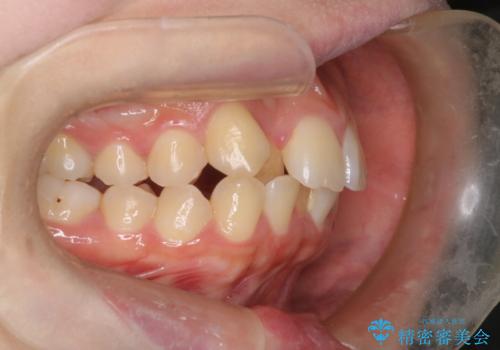

- 患者様は、結婚式までに歯並びを整えたいとのご要望で来院されました。診断の結果、上下左右の第一小臼歯を抜歯し、歯列全体を整える計画としました。審美性を重視し、目立ちにくいホワイトワイヤーを使用した矯正を提案しました。治療期間は2年を目安とし、結婚式までに前歯の整列と噛み合わせを優先的に整えるスケジュールで進めました。定期的な調整と経過観察を通じて、計画的に治療を進めました。